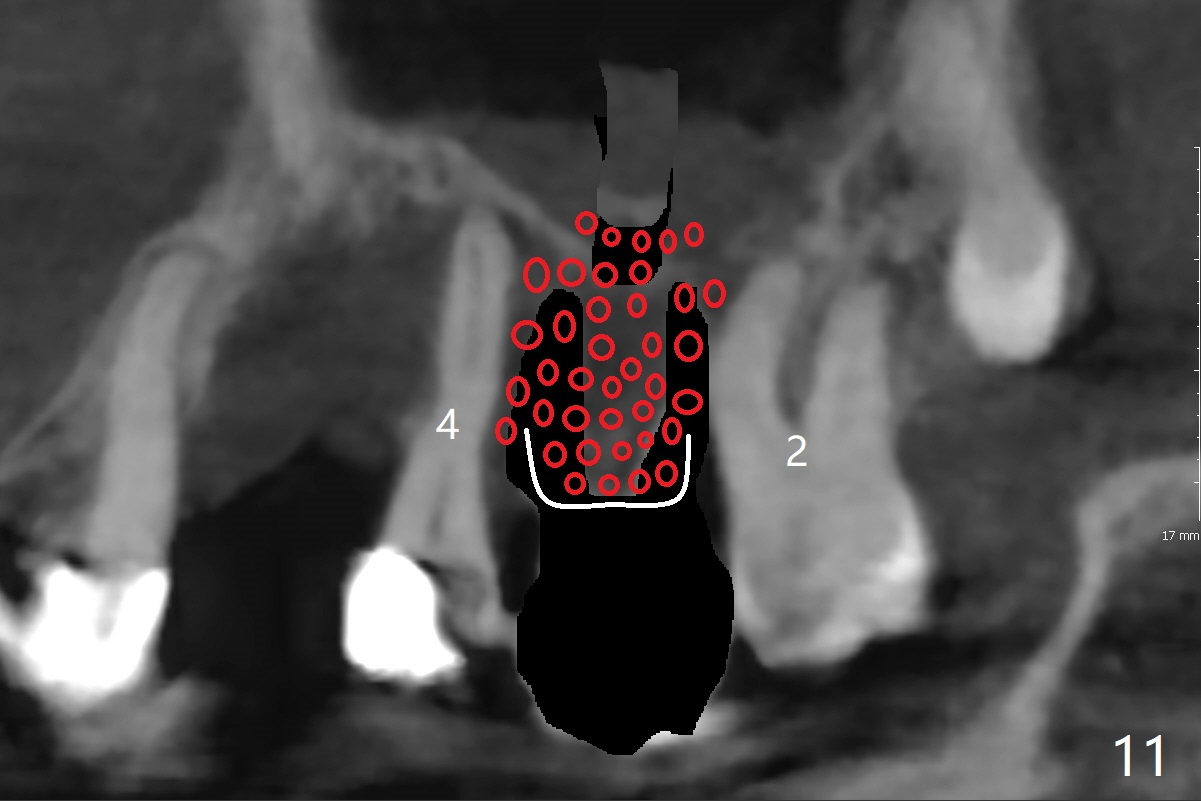

A 51-year-old woman has poor dentition with chronic periodontitis (Fig.1). She has financial constraint, but refuses RPD, insisting upon UR posterior implants first. After discussion of severe bone loss, she agrees with bone graft first (Fig.2-4). Since the bone atrophy is the most severe at #3 (Fig.5 coronal section; L: lingual), sinus lift (Fig.6 arrow) is conducted after extraction (black). Use sticky bone (Fig.7 red circles) and Titanium-reinforced Cytoplast (white) for socket preservation. Or if Magicore is able to achieve primary stability (Fig.8 green), an abutment (pink) will be placed for an immediate provisional (white). The latter are capable of holding bone graft in place. Since bone loss at #2 and 4 is less severe (Fig.9 sagittal section), their roots will act as walls to keep bone graft (Fig.11) in place after #3 extraction (Fig.10).